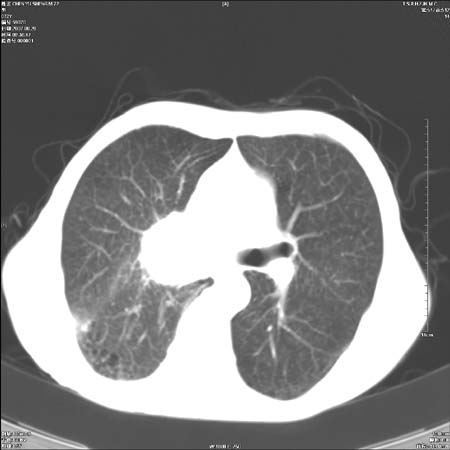

男性,72岁,既往肺结核,今复查。无前片对比。

右侧中央型肺癌伴中叶不张可能性大,建议增强扫描.右上肺陈旧性肺结核.慢性支气管炎伴肺气肿.右侧少量胸腔积液.

右侧中央型肺癌伴中叶不张可能性大,建议纤支镜检查.右上肺陈旧性肺结核.肺气肿。

典型右肺中心型肺癌

右侧中央型肺癌伴肺不张可能性大,建议增强扫描.右上肺陈旧性肺结核.慢性支气管炎伴肺气肿.右侧少量胸腔积液.

右肺中心型肺癌

右侧中央型肺癌.上肺陈旧性肺结核.

1右侧中央型肺癌伴中叶不张2右侧少量胸腔积液3右上肺陈旧性肺结核

1.右肺中心性肺癌并右肺中叶综合征2。右侧胸腔少量积液3。右肺上叶结核球已钙化,4。慢支伴肺气肿

右侧中央型肺癌伴中叶不张可能性大,建议纤支镜检查.右上肺陈旧性肺结核.肺气肿。

右侧中央型肺癌伴中叶不张可能性大,建议增强扫描.右上肺陈旧性肺结核.慢性支气管炎伴肺气肿.右侧少量胸腔积液.

右侧中央型肺癌伴中叶不张

右肺中央型肺癌伴右肺中叶不张。

右上肺陈旧性肺结核。

支持右肺中心型肺癌并中叶不张,右上肺陈旧性肺结核钙化,右侧少量胸腔积液。

支持右侧中央型肺癌伴中叶不张可能性大,建议增强扫描.右上肺陈旧性肺结核.慢性支气管炎伴肺气肿.右侧少量胸腔积液.

支持 1右侧中心型肺癌伴中叶不张2右侧少量胸腔积液3右上肺陈旧性肺结核4双肺局限性肺气肿

1,右侧中央型肺癌.

2,右上肺陈旧性肺结核.

1.右侧中央型肺癌伴中叶不张,建议纤支镜检查.

2.右上肺陈旧性肺结核.

3.肺气肿。

4.右侧少量胸腔积液.

右侧中央型肺癌伴中叶不张并纵隔淋巴结增大,建议增强扫描.右上肺陈旧性肺结核.慢性支气管炎伴肺气肿.右侧少量胸腔积液。

右肺中心型肺癌并肺不张,陈旧性肺tb.慢支,肺气肿.

陈旧性肺结核.慢性支气管炎伴肺气肿,中央型肺癌伴中叶不张。

右侧中央型肺癌伴中叶不张可能性大;右上肺陈旧性肺结核.慢性支气管炎伴肺气肿

陈旧性结核是存在,但真正致命的却是右侧中心型肺癌。